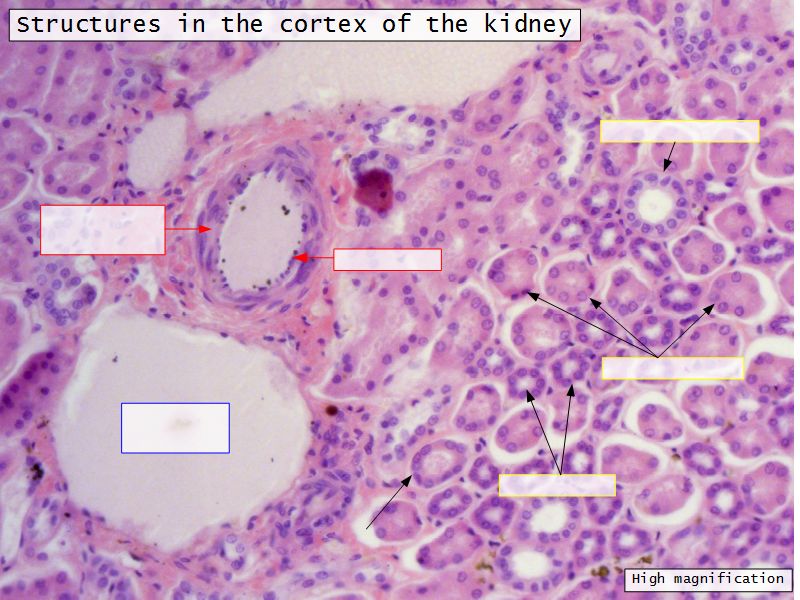

Appearance

- Cortex

- Renal corpuscles

- Convoluted tubules

Kidney lobule

- Group of neprons

- Open into branches

- Same collecting duct

- Not clearly demarcated

- Interlobular arteries/veins